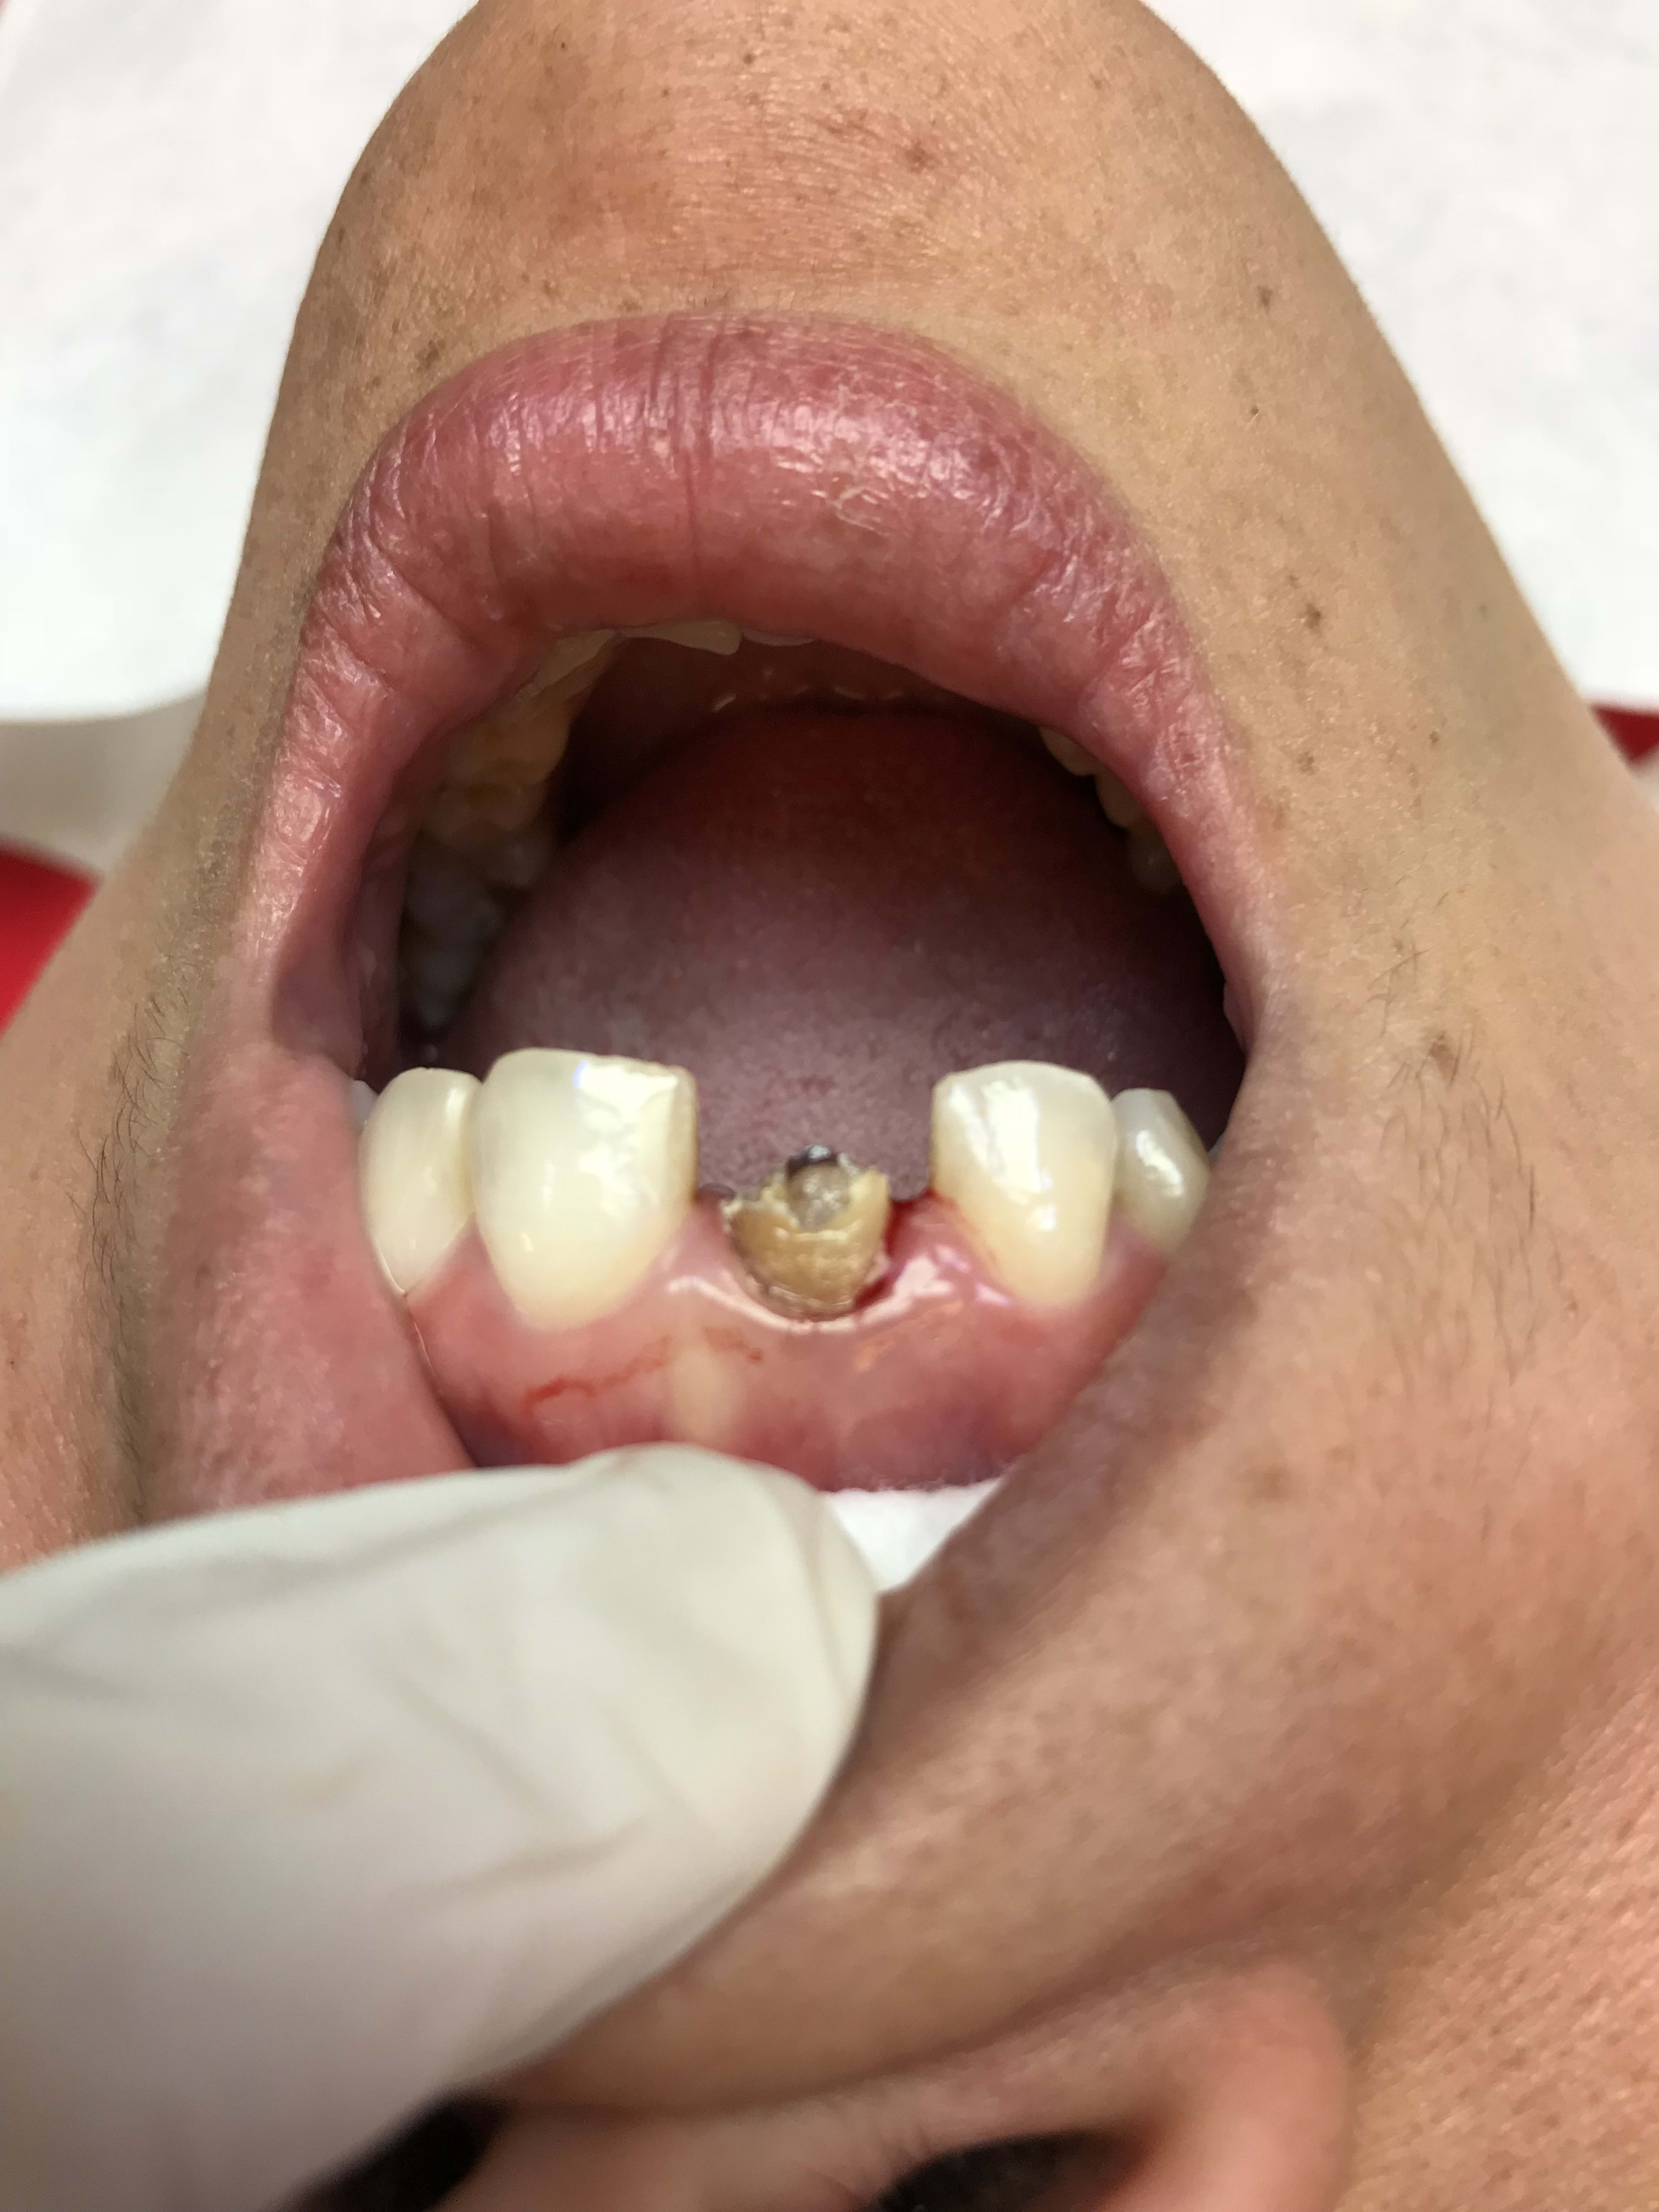

protection d'une plaie et de la suture.